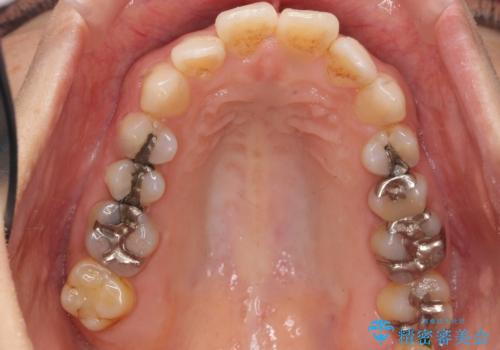

- 歯の根のあたりの歯ぐきを押すと痛むことを主訴に来院された患者様です。

精査したところ、左上の小臼歯(左上5)の神経が死んでいました。

根管治療後、セラミッククラウンによる補綴を行いました。

根管治療により症状がなくなり、またセラミッククラウンの自然な仕上がりにご満足頂けました。